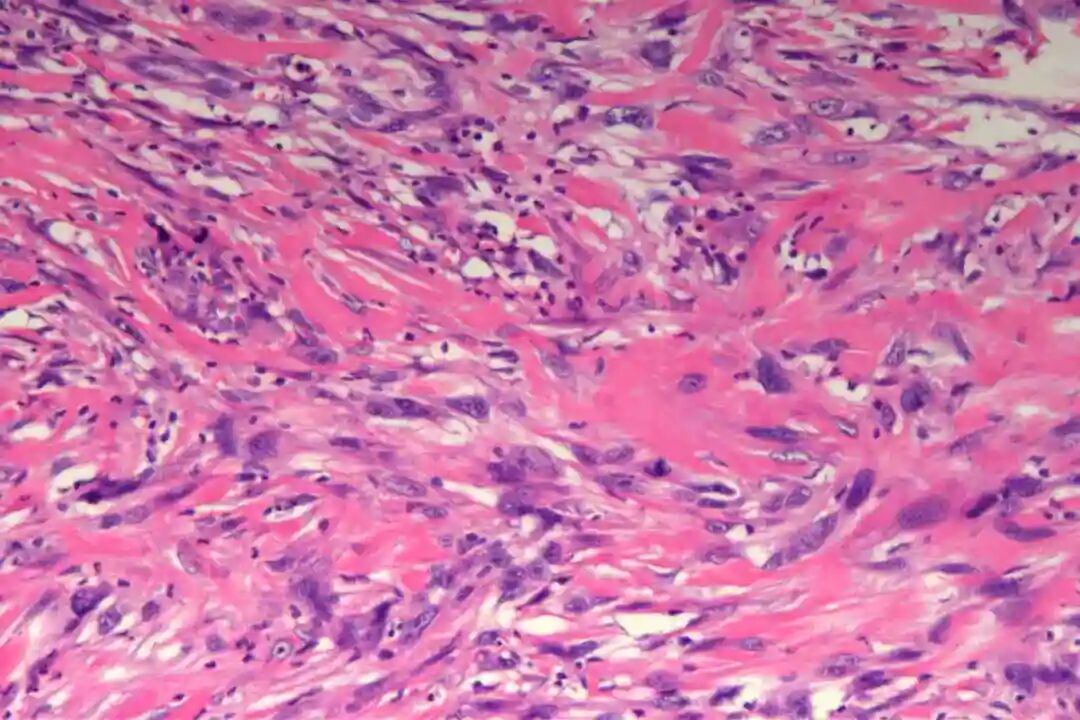

镜下表现

低倍镜:梭形细胞呈交织束状排列,浸润真皮深层或皮下脂肪

高倍镜:细胞核两端钝圆("雪茄形"),核异型性程度因分级而异;核分裂象(关键指标):低级别<5/10HPF,高级别≥5/10HPF;特征性胞质嗜酸性(肌源性分化)。

2、镜下特征

低倍镜:梭形细胞呈交织束状排列,浸润真皮深层或皮下脂肪。

高倍镜:细胞核两端钝圆("雪茄形"),核异型性程度因分级而异;

核分裂象(关键指标):低级别<5/10HPF,高级别≥5/10HPF;特征性胞质嗜酸性(肌源性分化)。